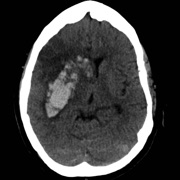

The HeRS (Hemorrhage Risk Stratification) calculator is an application that aids in determining the probability of hemorrhagic transformation of acute ischemic stroke in patients with an indication for anticoagulation. It is a prospectively validated score.

The HeRS score is a prospectively validated equation based on continuous variables of age, renal function, and stroke size. The equation is complex and cannot be performed easily or quickly with paper or with an ordinary calculator. Determining the probability of hemorrhagic transformation of acute ischemic stroke is clinically useful as risk of hemorrhage often needs to be weighed against risk of recurrent stroke in deciding on whether or not to anticoagulate in the acute clinical setting. The HeRS score provides one of these valuable pieces of data- the likelihood of hemorrhagic transformation. Using the mobile application, the HeRS score can be accurately and easily determined rapidly.